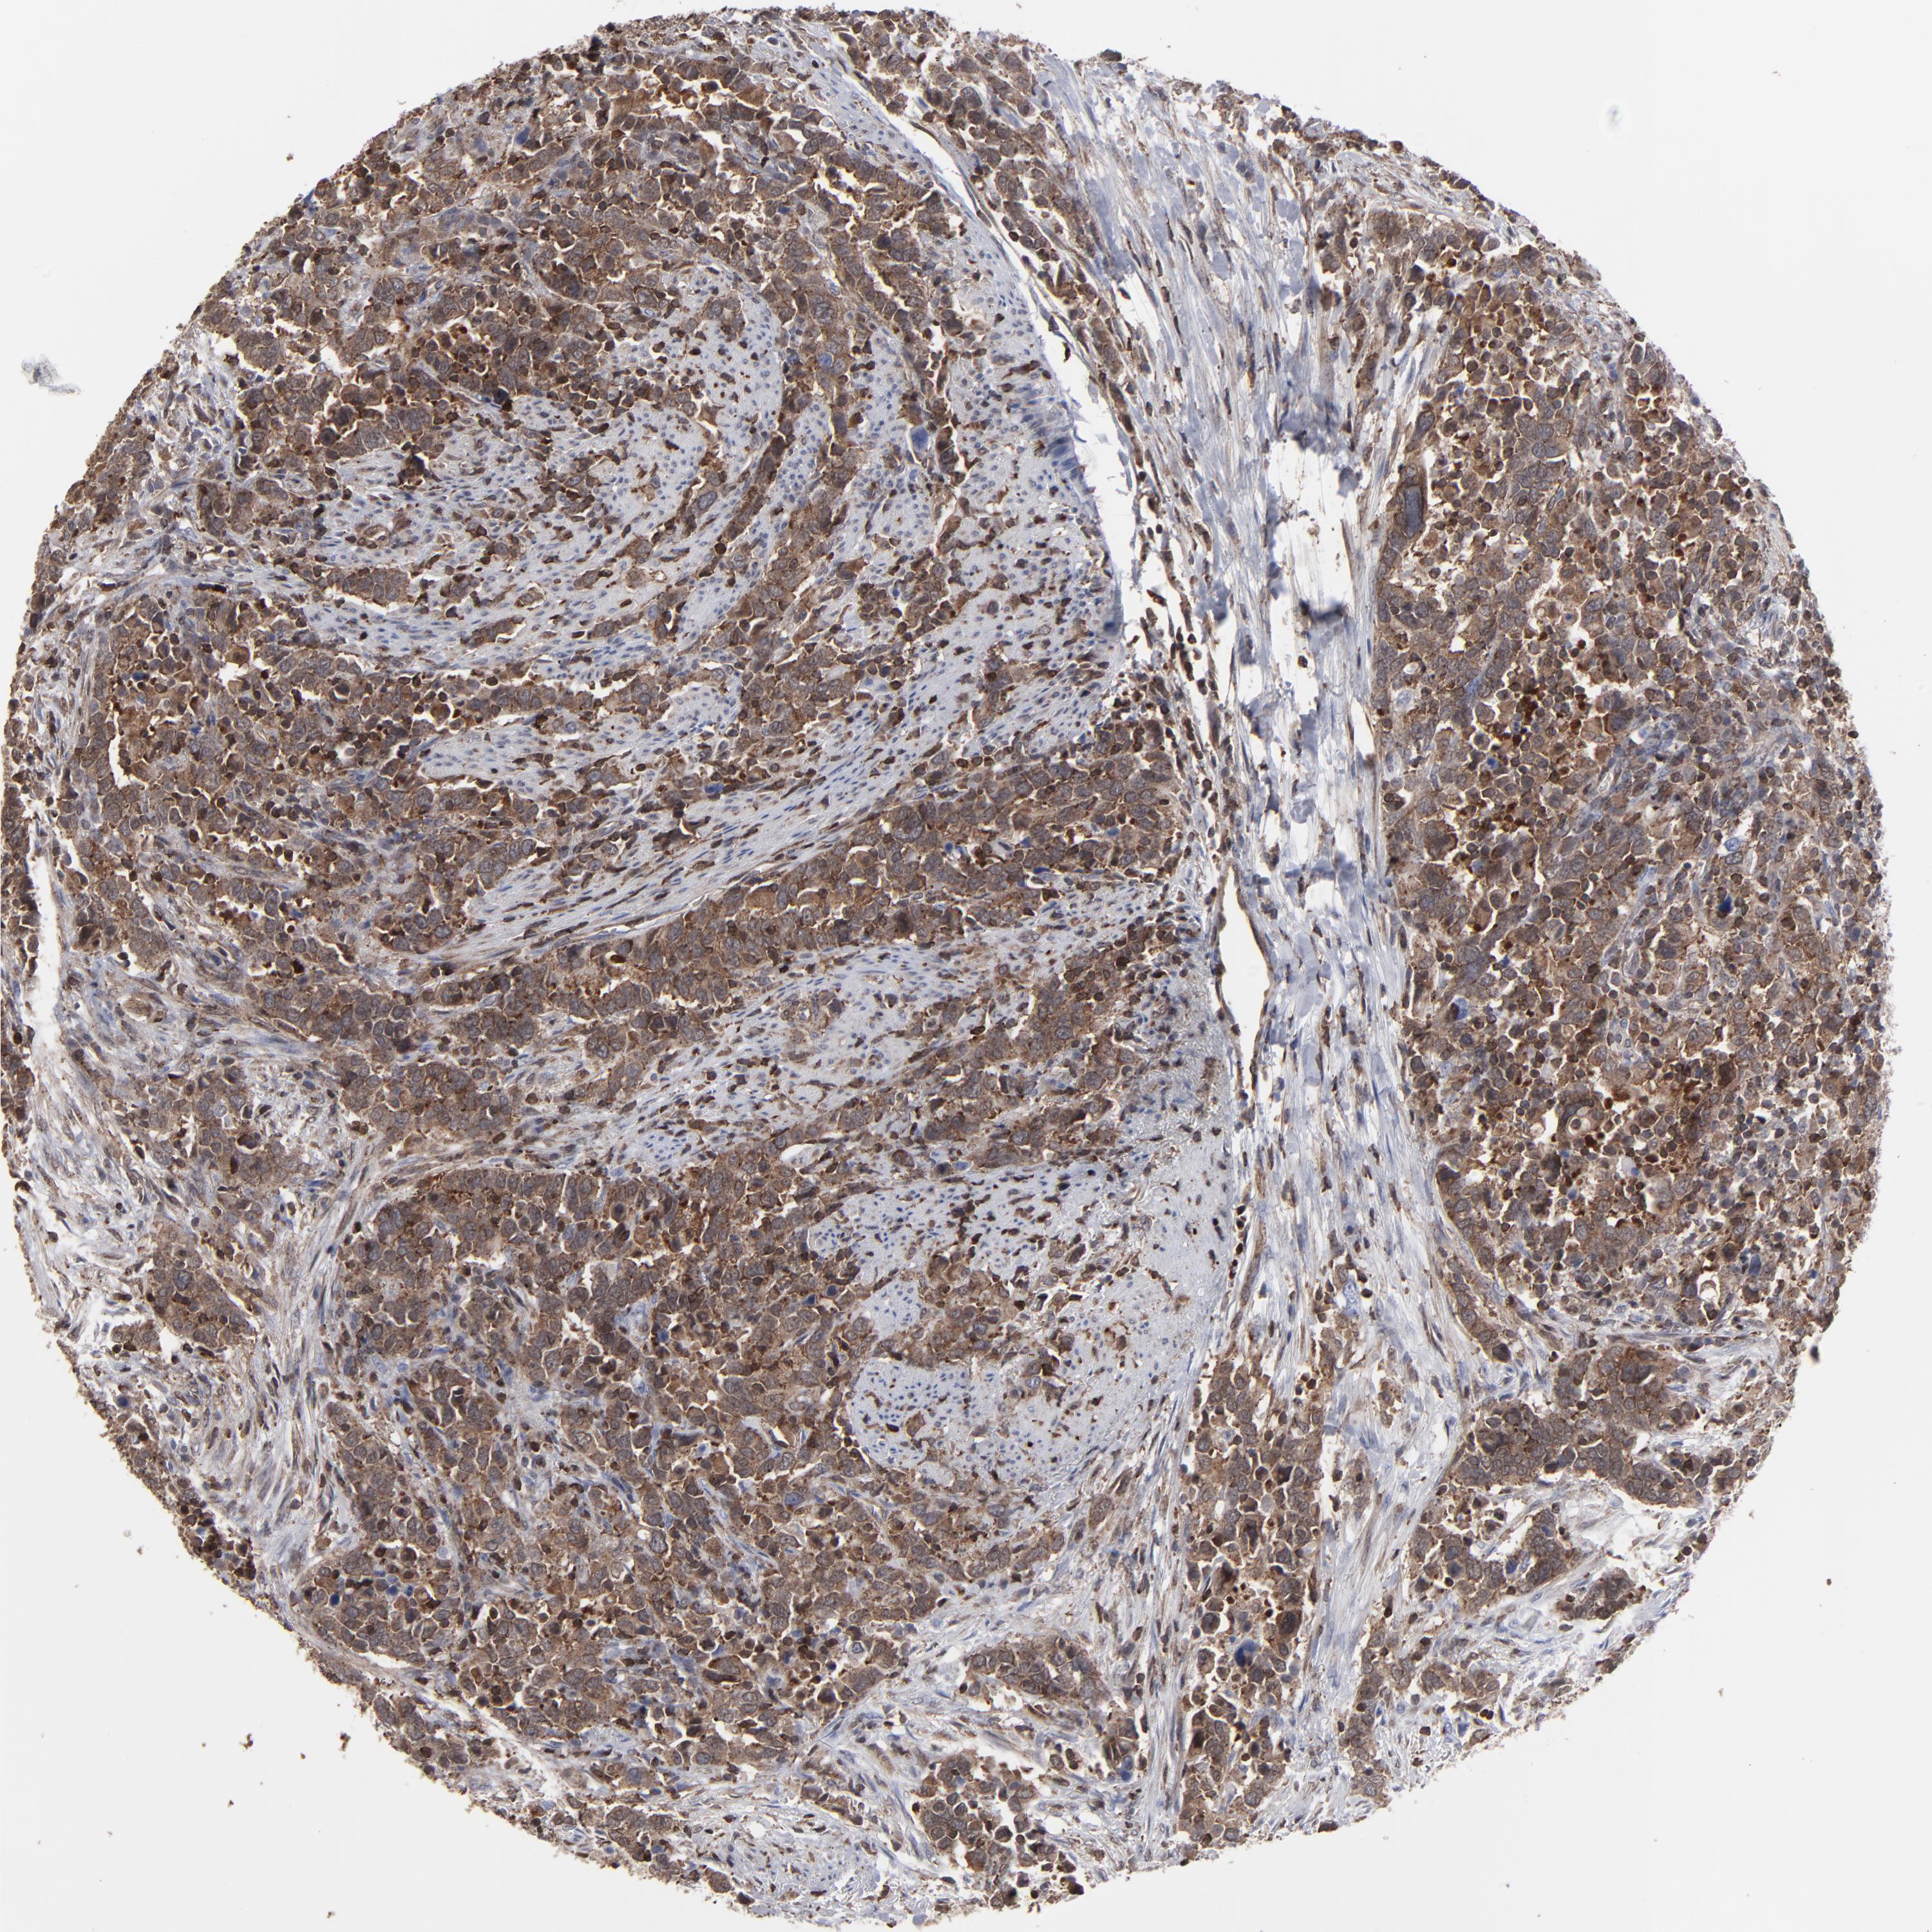

UROTHELIAL CANCER - Protein expressioni

A mouse-over function shows sample information and annotation data. Click on an image to view it in a full screen mode. Samples can be filtered based on level of antibody staining by selecting one or several of the following categories: high, medium, low and not detected. The assay and annotation is described here.

Antibody stainingi

Antibody staining in the annotated cell types in the current human tissue is reported as not detected, low, medium, or high, based on conventional immunohistochemistry profiling in selected tissues. This score is based on the combination of the staining intensity and fraction of stained cells.

Each image is clickable and will lead to virtual microscopy that enables deeper exploration of all samples and also displays staining intensity scores, fraction scores and subcellular localization as well as patient and tissue information for each sample.

Antibody HPA002109

Staining

High

Medium

Low

Not detected

Intensity

Strong

Moderate

Weak

Negative

Quantity

>75%

75%-25%

<25%

None

Location

Nuclear

Cytoplasmic/membranous

Cytoplasmic/membranous,nuclear

Urothelial carcinoma, High grade

Urothelial carcinoma, Low grade